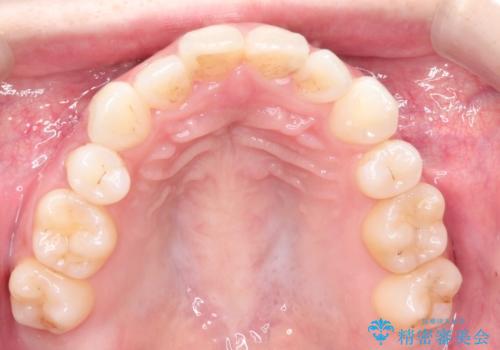

前歯の後戻りを部分矯正で整った歯並びへ

- 矯正治療後の上の前歯の後戻りを気にされて来院されました。

上の前歯のみにブラケットをつけて矯正治療を行いました。